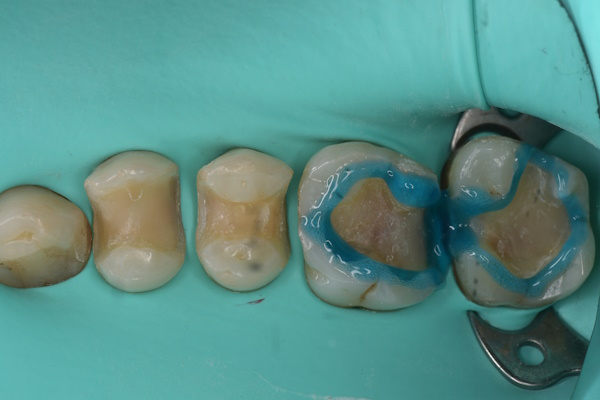

エッチング後(1回目)